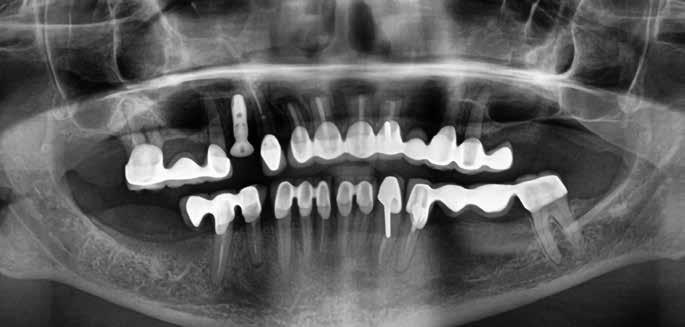

A műtéti tervezéshez mindkét esetben CBCT-felvételt használtunk, majd az utánkövetési időszakban periapikális röntgenfelvételekkel ellenőriztük az implantátumokat. A fogeltávolítást követően azonnali implantáció történt, az alveolus fala és az implantátum felszíne közt fennmaradó réseket csontpótlóval töltöttük ki. A három hónapos gyógyulás leteltével az ideiglenes koronákat eltávolítottuk, A-szilikonnal lenyomatot vettünk, majd három lítium-diszilikát és egy monolitikus cirkónium-dioxid korona készült. A páciensek utánkövetése mindkét esetben minimum tizenkét hónap volt, amelynek során valamennyi implantátumot klinikailag és radiológiailag is sikeresnek ítéltünk az osszeointegráció, a marginális csont stabilitása és a periimplantáris szövetek egészsége tekintetében.

1. a–d. ábrák: Kiindulási klinikai állapot a két páciens esetében: Az első páciensnél a jobb felső premolárisok és az első moláris, a második páciensnél a bal felső második premoláris.

heléssel vagy anélkül). Az első páciensnél gyökérreszorpció miatt szükségessé vált a jobb felső premolárisok és az első moláris eltávolítása (1. a–b ábrák). A második páciensnél a bal felső második premoláris frakturát szenvedett (1. c–d ábrák) Az átfogó tervezést és diagnosztikát CBCT-felvétel segítségével végeztük (2. a–c ábrák), a posztoperatív kontroll és az utánkövetés időszakában pedig periapikális röntgenfelvételeket készítettünk. A jelen tanulmányban résztvevő valamennyi páciens nemdohányzó volt, jó, vagy gyógyszeresen jól karbantartott általános egészségi állapotnak örvendett. A hatékony plakk-kontroll ellenére műtét előtt mindkét páciensnél végeztünk supragingivális depurálást és gyökérsimítást.

2. a–c ábrák: Kiindulási CBCT-felvételek.

A végleges ragasztást követően röntgenfelvételt készítettünk, amelyet összevetettünk a közvetlenül a műtét után készült felvételekkel: a marginális csontszint változatlan volt. A pácienseket 14 hónapon keresztül rendszeresen visszahívtuk. Klinikai és röntgenvizsgálattal sem tapasztaltunk komplikációt (12. a–b ábrák)

10. a ábra: Végleges lítium-diszilikát koronák. – 10. b ábra: Végleges monolitikus cirkónium-dioxid korona. – 11. a–b ábrák: Klinikai megjelenés tizenkét hónap elteltével. 12. a–b ábrák: Tizenkét hónapos kontrollröntgen-felvételek.